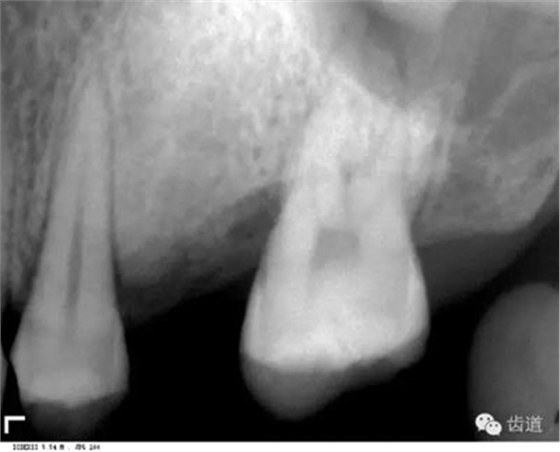

位于前磨牙根尖區(qū)域,為一大致圓形密度低的影像。頦孔位置變異大,多位于第二前磨牙根尖稍下,注意與根尖周病變區(qū)別,其要點(diǎn)是牙周膜及其骨硬板是否連續(xù)不斷。